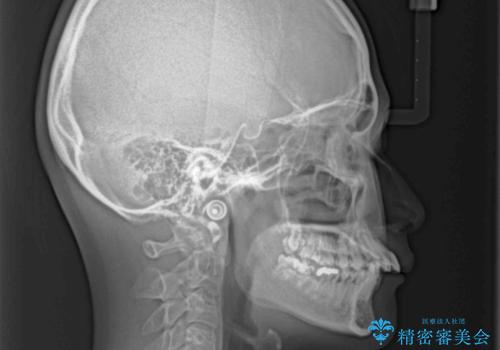

- 前方に飛び出した前歯と、下顎の八重歯を気にして来院された患者様です。

口元の突出感を改善するため、上下左右の第一小臼歯4本を抜歯し、ワイヤー装置にて矯正治療を行うこととしました。

抜歯矯正により、口元の印象だけでなく、横顔の印象も大きく改善されました。